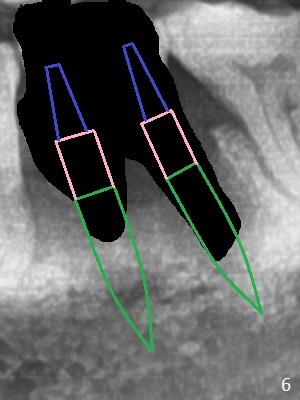

A 63-year-old man is a diabetic with history of good control. He masticates unilaterally with missing teeth #2,3 and 24 (Fig.1 (taken 5 years ago)). The latter has been restored with an implant. Last February the mesial root of the tooth #19 was found to have vertical fracture with bone loss until the base of the septum (Fig.2). The bone available for implantation is ~7-8 mm after root fracture (Fig.3,4). The initial osteotomy depth will be 7 mm (IS kit), followed by the calibrated parallel pin. The latter determines how many millimeters of an implant will be surrounded by the graft bone (Fig.4,5 (green: implant length; pink: cuff; blue: abutment length)). Since the buccal defect is severe with mesial root split (Fig.7 *), draw blood for PRF (2 large tubes). To save the remaining septum, place 2 of 1-piece implants on the either side of the septum (compare Fig.6,8). Take photos to compare buccal vs. lingual gingival recession. Tell the patient that the tooth #20 may be nonsalvageable. Since insurance preauthorization does not get approval for several times, the tooth #19 is extracted with socket preservation and periodontal dressing. The latter dislodges in 1 day. When the patient returns for follow up 4 days postop, the socket is exposed (Fig.9). An immediate implant should have been placed to keep the graft in place. PRF also helps. In fact preauthorization letter arrived 1 day earlier. It appears that guided surgery is indicated for limited bone height. The bone graft appears to gain ~ 5 mm bone in 4 months (Fig.10), which allows to place a 5x8.5 mm implant (Fig.11).